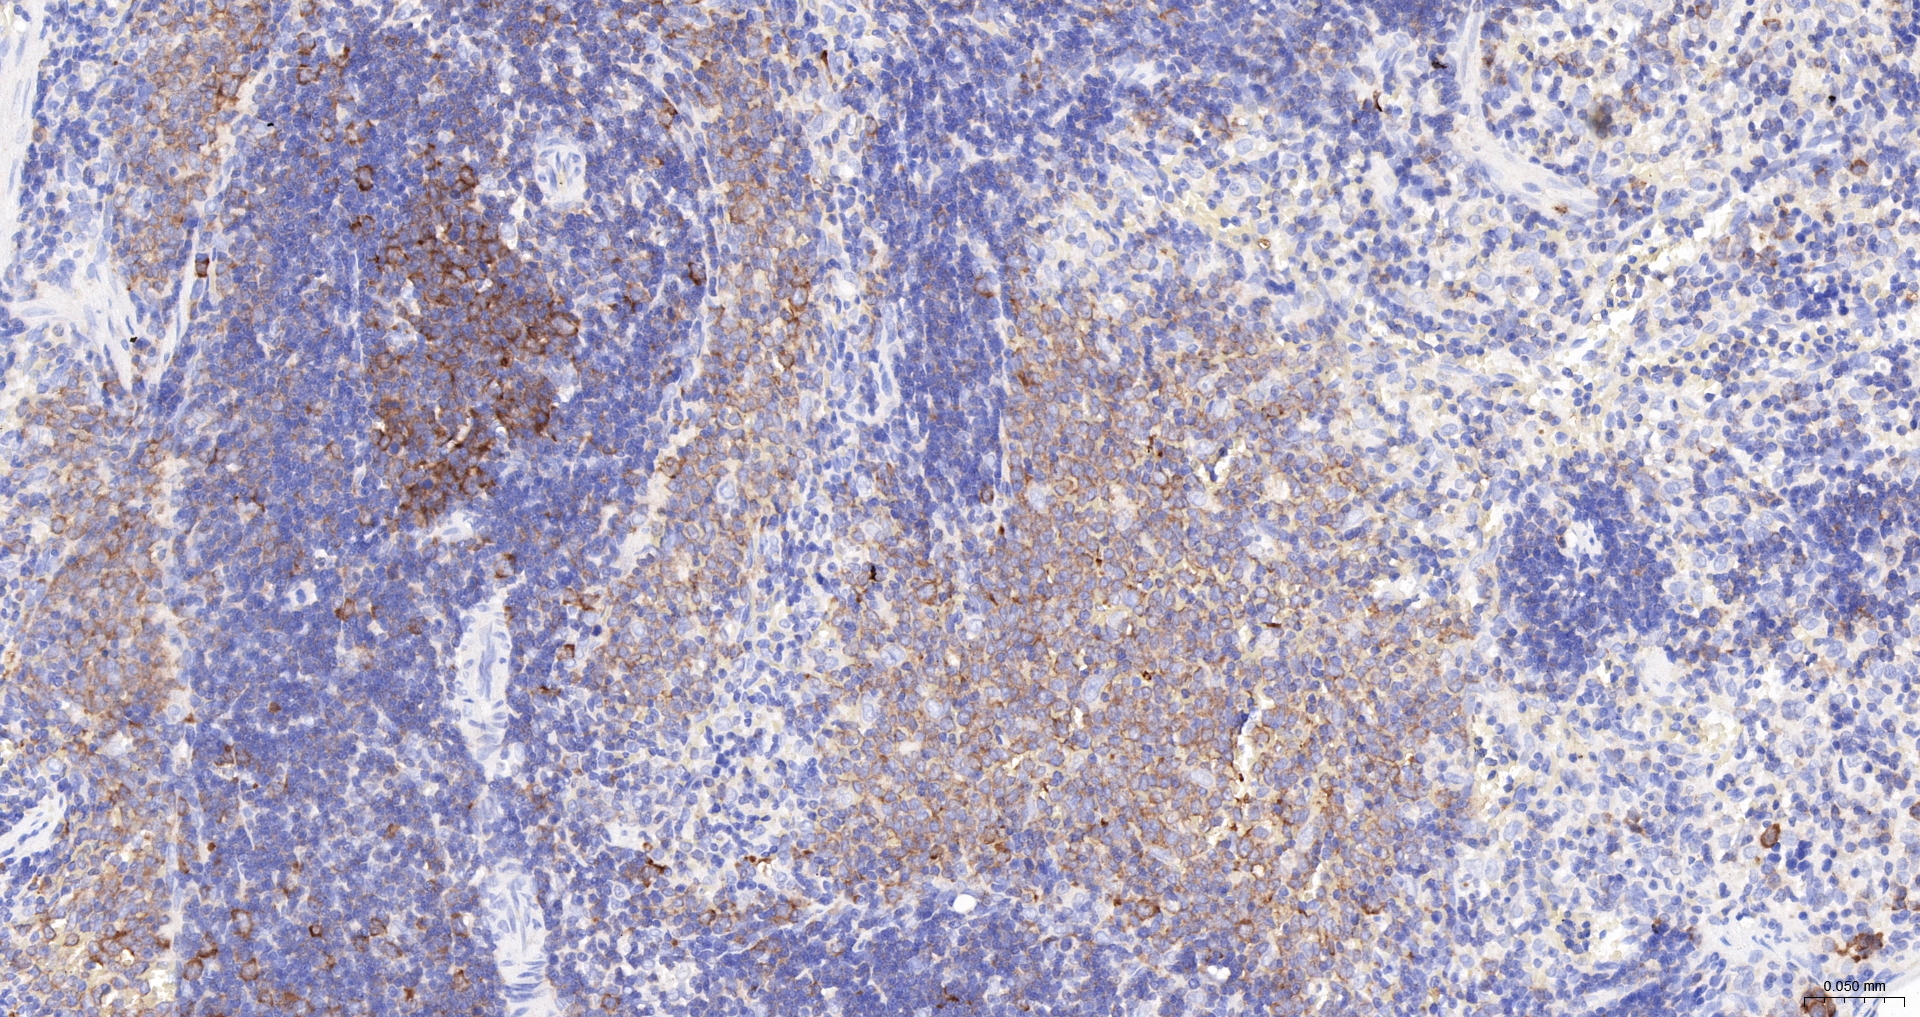

IHC-P IHC-P1:100-500

IHC-F IHC-F1:100-500